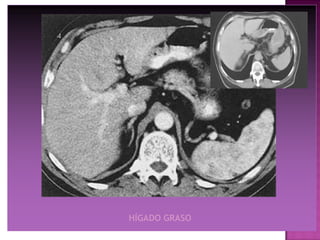

HÍGADO GRASO